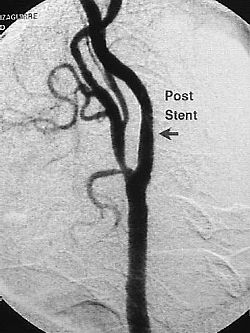

Una manera muy frecuente de la disminucion del flujo es una estenosis (estrechamiento) como se observa en arteriografias inferiores.

Arteriografias tronco carotideo  comun  con sus respectivas ramas int. externa.

Se muestra estenosis A. carotida y posterior angioplastia con recuperacion de espacio luminar.